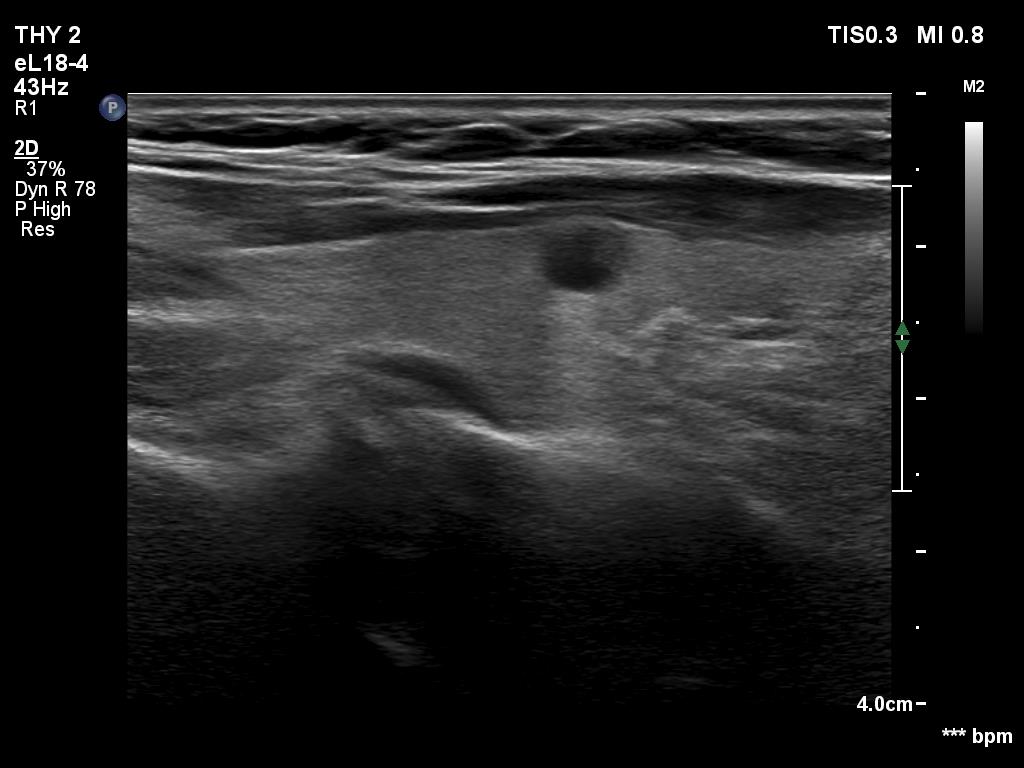

Parathyroid lesions - case 1618

Follow-up investigation 6 months after first visit (ultrasonographic picture 3)

Right lobe, longitudinal view.